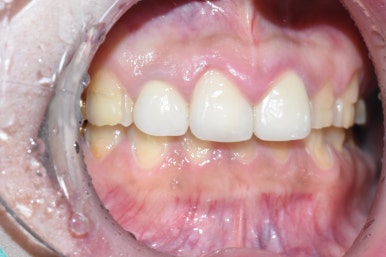

환자분이 정말 새하얗게 치아를 만들어 달라고 하셨기 때문에

새하얀 색으로 들어갔습니다.

사실 치과 종사자들은 이런 불투명한 하얀색은 자연스럽지 않아서 좋아하진 않고

저희 치과에서도 보통 자연스러운 색으로 들어가긴 하는데

단지 색상이 엄청 하얗고 불투명하다고 해서 치아건강에 문제를 주는 것은 아니기 때문에

환자분의 기호에 맞춰드렸습니다.

이렇게 불투명한 색은 미백으로는 거의 나올 수 없고

미백은 본인의 치아 자체에 하는 것이다 보니 한계가 있습니다.

라미네이트나 크라운 같은 붙이는 인공 보철이기 때문에 가능한 것이구요.

또한 환자분이 입을 벌렸을 때 보이는 앞니부터 작은 어금니까지 엄청 많은 치아를 쭉 하기를 원하셨기 때문에

치아 한두개만 하얗게 하면 튀겠지만

이분의 경우 여러개 다수 치아를 하기 때문에 하얗게 해도 치아 하나만 튀는 건 아니라서

환자분의 당부에 맞게 아주 하~얗게 만들어드렸습니다!

또한 크라운과 라미네이트의 재료가 다르다 보니 색을 거의 같게 맞추는 데에 한계가 있을 수 있는데

최대한 맞춰드렸습니다.

모양도 기존에 크라운만 튀던 모양에서 → 귀엽고 환자분의 이미지에 맞는 모양으로 만들었습니다.

기존의 윗니 크라운이 아랫니를 너무 많이 덮어서 어색해보이던 모습도 개선하였습니다.